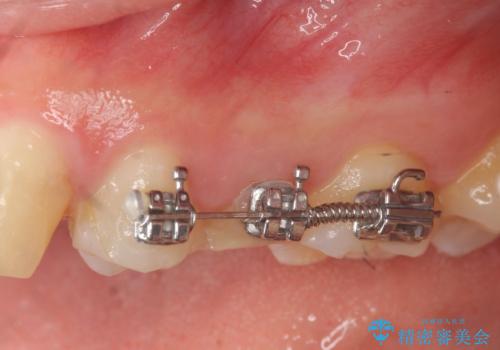

- 部分ワイヤー矯正

虫歯が大きかったことから、神経の温存はできたものの歯ぐきよりも深い虫歯の問題を解決するため部分矯正治療を併用したセラミック治療を行うこととしました。

当初、歯ぐきよりも深い虫歯のぞんざいや、歯のポジションに問題がありましたがマルチブラケットを用いた部分矯正を行うことで適切な位置へと歯を移動させ、歯周環境を整えたセラミック治療を行うことができました。